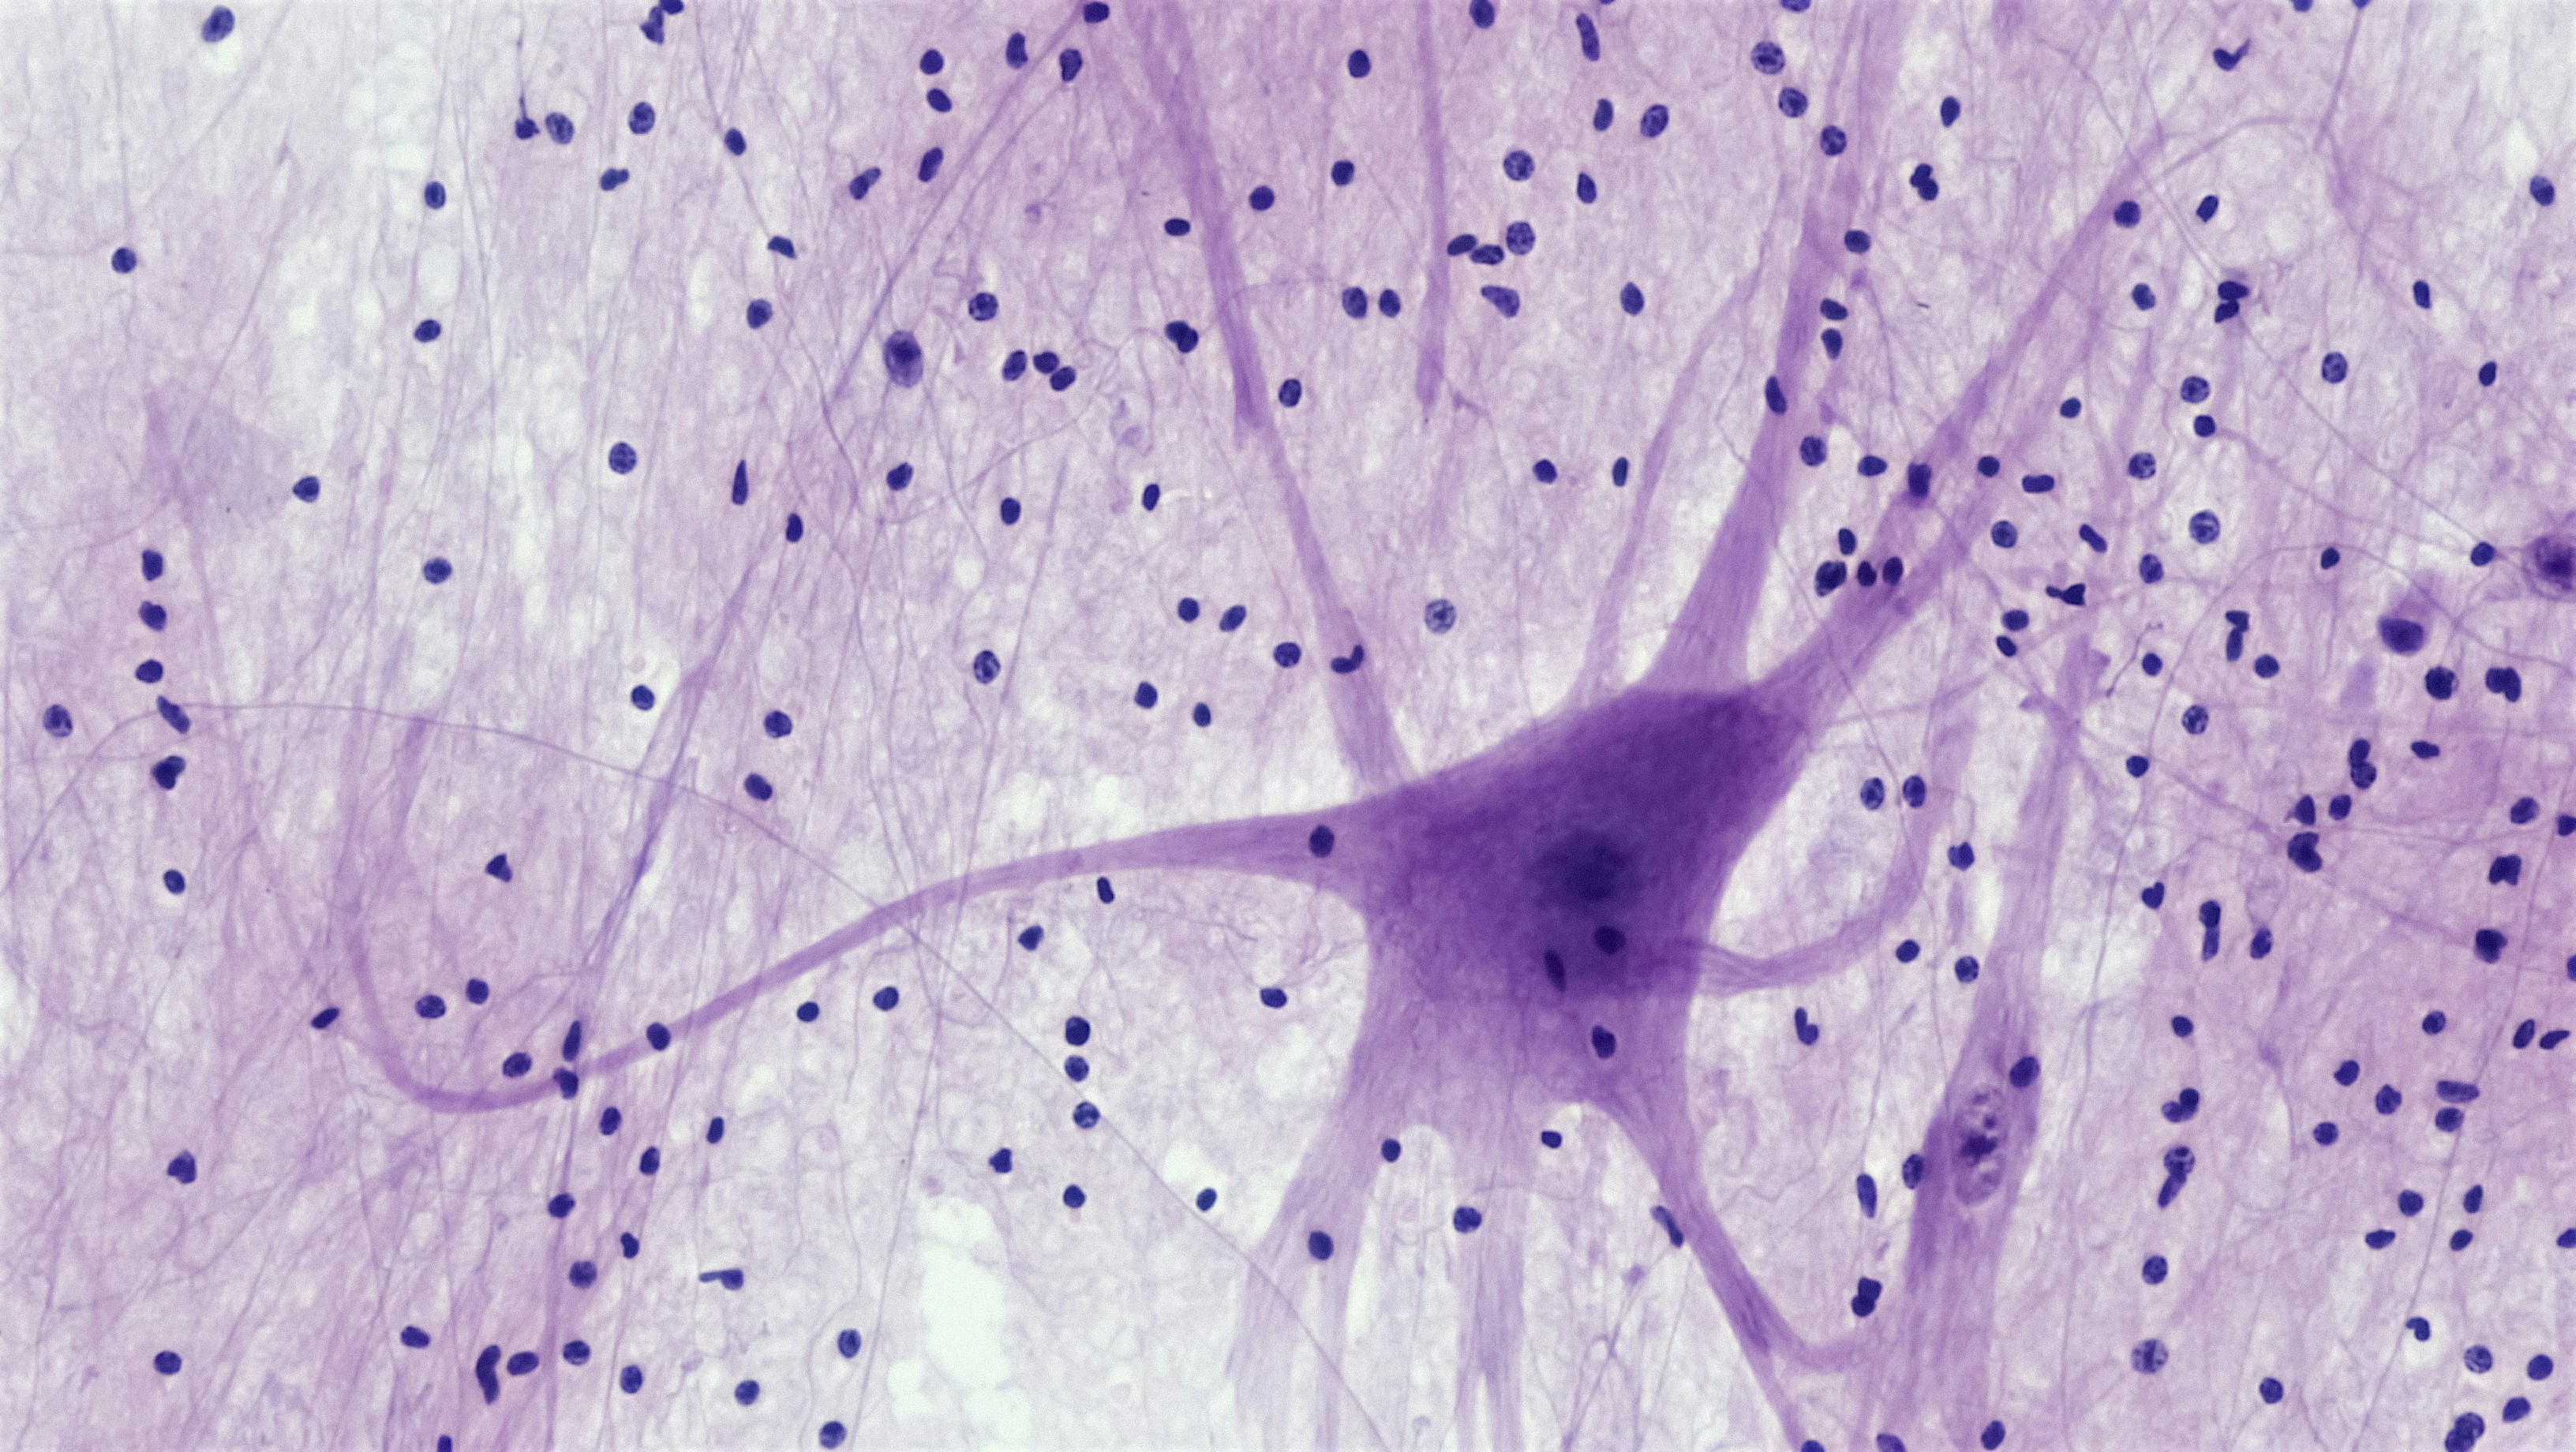

Optimización de redes neuronales en microcircuitos corticales para mejorar su eficiencia y precisión en el procesamiento de información.